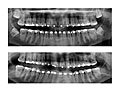

Your dentist will check for signs of a wisdom tooth coming through your gum or crowding other teeth. You will have X-rays to find out if your wisdom teeth are causing problems now or are likely to cause problems in the future.